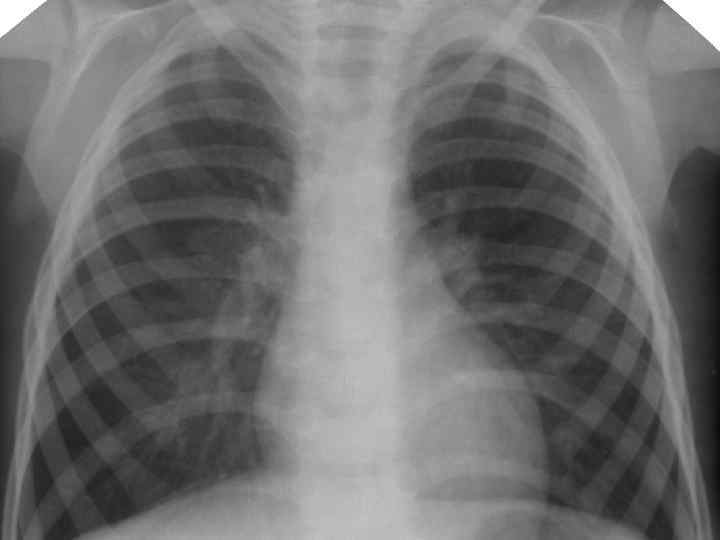

Клинические особенности туберкулеза у взрослых на фоне ВИЧ-инфекции ► ► ► ► ► Внутригрудные аденопатии; Милиарные высыпания; Частое поражение базальных сегментов легких; Относительно редкое поражение каудоапикальных сегментов легких; Распад легочной ткани диагностируется в 2 раза реже; Нередок плевральный выпот; Велика склонность к генерализации туберкулезной инфекции с множественными внелегочными локализациями. Присоеднинение туберкулезного менингита; МБТ в мокроте выявляются одинаково часто у ВИЧ негативных и позитивных лиц, по крови МБТ методом посева выделяются у 70% пациентов; При отсутствии признаков локального туберкулеза и неясной лихорадке – посев костного мозга часто дает МБТ+.

Клинико-эпидемиологические особенности туберкулезной инфекции у ВИЧинфицированных и больных СПИДом детей ► Вертикальный путь заражения ВИЧ; ► Ранний возраст; ► Семейные контакты с болеющими туберкулезом в активных фазах; ► Отсутствие вакцинации БЦЖ; ► Выраженный локальный процесс, протекающий с: § бронхолегочными поражениями; § Распадом легочной ткани; § Обсеменением легочной ткани.

Неблагоприятное сочетание ряда обстоятельств: § Ранний возраст; § Тяжелые семейные контакты; § Отсутствие вакцинации - и у свободных от ВИЧ-инфекции детей всегда приводят к развитию локального туберкулеза, протекающего, как правило, ОСЛОЖНЕННО с бронхолегочными поражениями, распадом легочной ткани, диссеминациями.